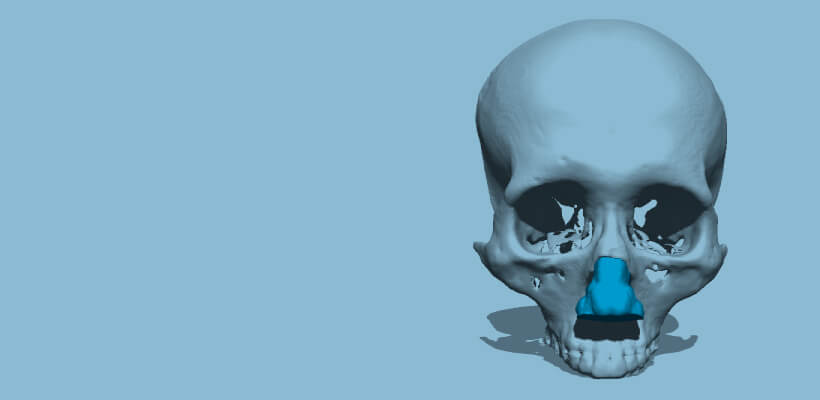

Preoperative simulation

Cosmetic surgery, Nose

A cranial model that can reproduce the cartilage part of the nose can be simulated in advance.

While most of the models for verification of medical devices used to be made of plaster, in recent years, there has been an increasing demand for soft and transparent models that are closer to the human body. Silicon materials can now reproduce blood vessels, nerves, and cartilage of the nose of the living body, and epoxy light-curing resin materials can be used to make transparent models, so that the inside of the model can be visually checked and the procedure can be confirmed in real time. The bone model can be used not only by medical professionals to confirm procedures and formulate treatment plans through preoperative simulation, but also by medical device manufacturers as a development tool, sales promotion tool, marketing tool, and internal training tool. It can also be used as a development tool for medical device manufacturers, a sales promotion tool, a marketing tool, and an internal training tool.